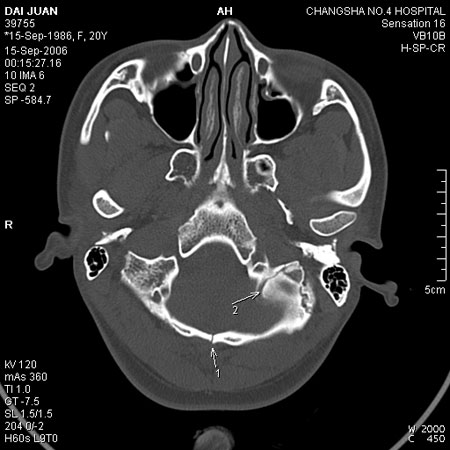

上图

箭头1:骨缝

箭头2:骨折不能排除